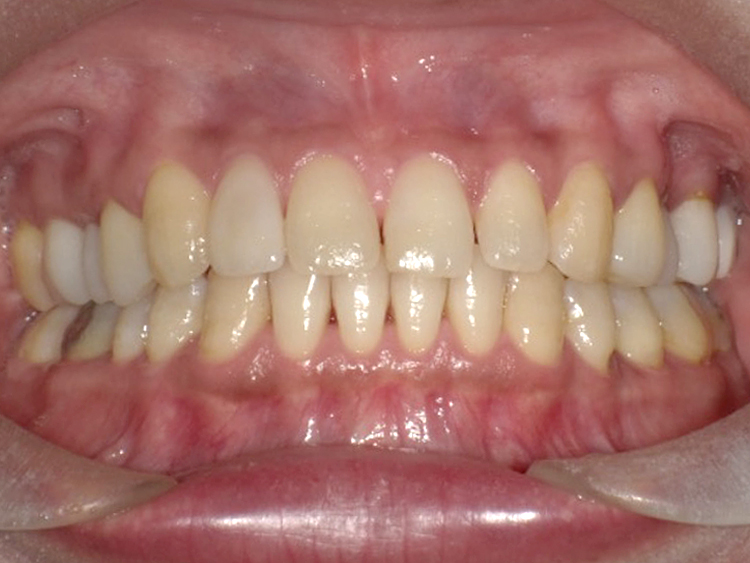

症例3

Before

After

| 主訴 | 上下の歯のガタガタを治したい |

|---|---|

| 年齢 | --- |

| 治療期間 | 約10ヶ月 |

| 治療内容 | インビザラインiGoで上下顎の治療。 狭まっていた歯並びを広げることで、 ガタガタに並んでいた歯を綺麗に並べた。 |

| 治療費 | ¥517,000(税込)+月額調整料 |

| 治療のリスク | 歯と歯の間を削ることでスペースを確保するので、 場合によっては歯が染みる症状が出ることがある。 |